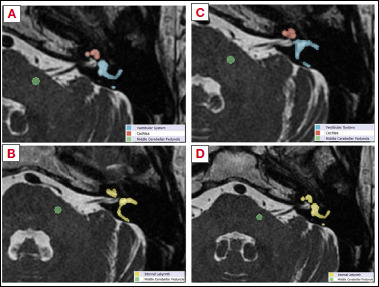

Methods: 26 patients with unilateral vestibulocochlear deficits underwent hearing and vestibular assessments and were categorised into severity classes using audiological and vestibular deficit scores. Normalised signal intensity values of inner ear structures were extracted from 3D-T2-WI-MRI scans (nT2mean, nT2Max, nT2min) and signal intensity ratios were calculated using the unaffected ear as a reference.